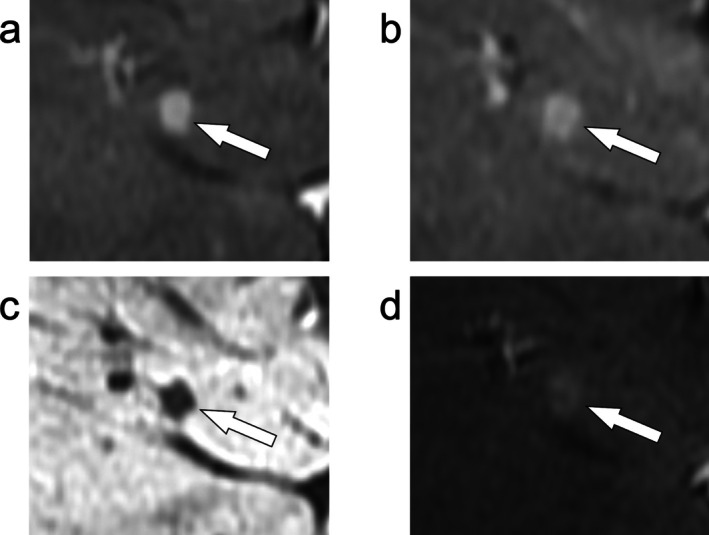

美国放射学会肝脏影像学报告和数据系统(LI-RADS)是对肝细胞癌高危患者肝脏影像学观察进行分类和风险分层的卓越框架。本文综述了肝细胞癌的发病机制和MRI在LI-RADS中的应用,具体包括LI-RADS诊断算法,其组成部分,以及参考最新支持证据的可重复性。综述了LI-RADS治疗反应算法,包括最近的放射治疗反应算法。探讨了人工智能的应用,争议点,LI-RADS相对于其他肝脏成像系统,以及可能的未来方向。通过阅读本文,读者将对LI-RADS的基础和应用以及可能的未来方向有一个了解。

The American College of Radiology Liver Imaging Reporting and Data System (LI-RADS) is the preeminent framework for classification and risk stratification of liver observations on imaging in patients at high risk for hepatocellular carcinoma. In this review, the pathogenesis of hepatocellular carcinoma and the use of MRI in LI-RADS is discussed, including specifically the LI-RADS diagnostic algorithm, its components, and its reproducibility with reference to the latest supporting evidence. The LI-RADS treatment response algorithms are reviewed, including the more recent radiation treatment response algorithm. The application of artificial intelligence, points of controversy, LI-RADS relative to other liver imaging systems, and possible future directions are explored. After reading this article, the reader will have an understanding of the foundation and application of LI-RADS as well as possible future directions.